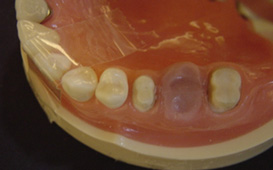

長牙橋導致蛀牙 - 案例三

拆下牙橋後